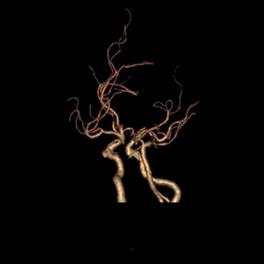

病例38:烟雾病合并右侧大脑前动脉A2段开窗畸形